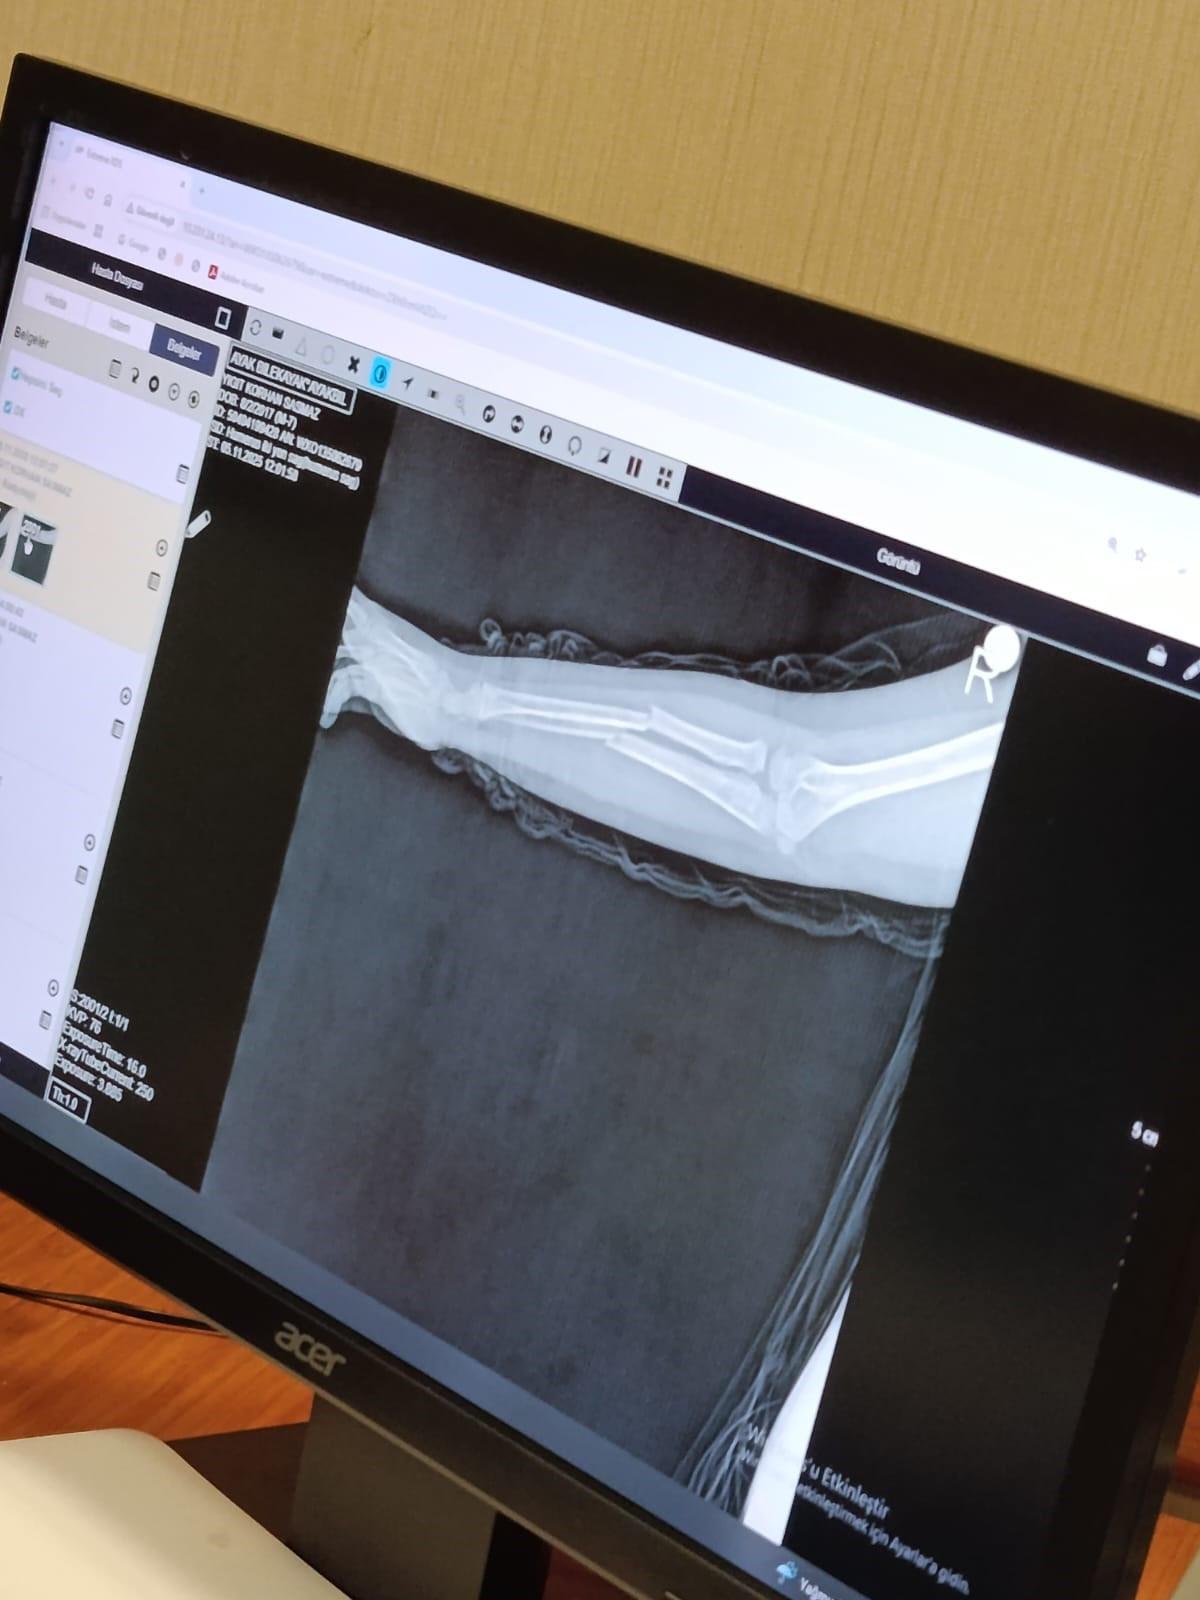

İddiaya göre, Y.K.Ş. (8) okulda bir süredir kendisini rahatsız eden 9 yaşındaki çocuk tarafından darbedilerek kolu ikiye katlandı.

Y.K.Ş.'nin 2'ye katlanan kolu 2 ayrı yerinden kırıldı.

Oğlunu okuldan alıp hastaneye götüren anne Songül Gökdemir, oğlunun kolunun 2 ayrı yerinden kırıldığını öğrenip ameliyata alınacağını öğrendi.

Eğitimi aksayan çocuğun 2 hafta sonra ise platinlerinin çıkarılması için yeniden ameliyata gireceği öğrenildi.